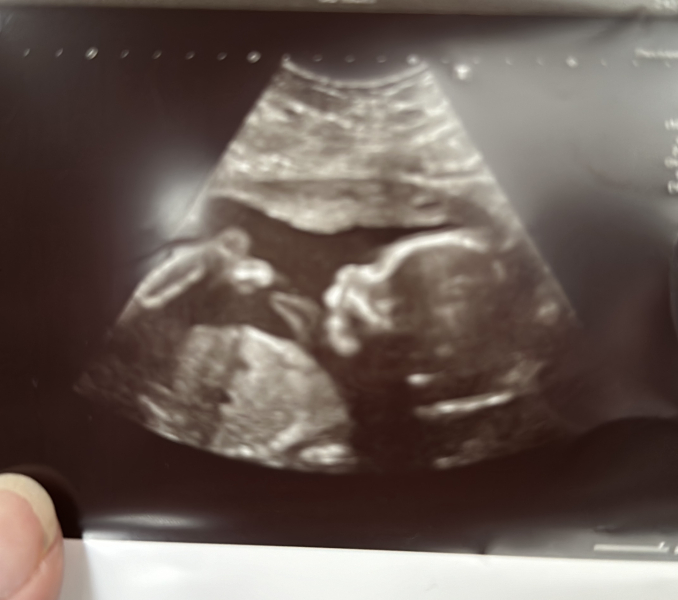

BabyD6 · 30/10/2023 15:02

Had my 20 week scan today (I am 20+5). Baby all good and growing perfectly. Thought I’d post my scan photo here as made us giggle. Looks like the baby is telling me to be quiet 🙊 Also looks like baby has big biceps haha!

@Busylizzie85 How did your scan go?

@BabyD6 that's such a fab scan photo. Haha I love the 'shh' pose , so cute

@BabyD6 Your scan is amazing! Love it 😆 Mine's on Thursday.

@BabyD6 thats such a great scan photo!